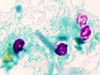

Balantidium coli (trophozoite)

Balantidium coli (trophozoite)

Balantidium coli (cyst)